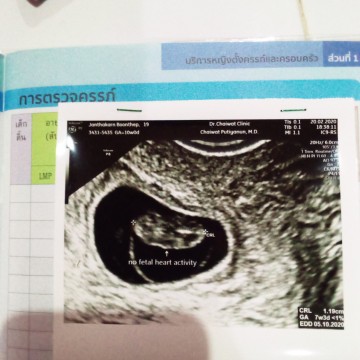

คุณแม่เตรียมใจยังไงค่ะไปนัดคุณหมอมาเเล้วชาวช่องคลอดมาแต่ไม่พบหัวใจเด็กเต้นตอนนี้รอนัดอีกทีก็27นุ้นตอนนี้เครียดมากเพราะเคยเเท้งมาก่อนไม่อยากเสียลูกคนนี้อีกแล้ว